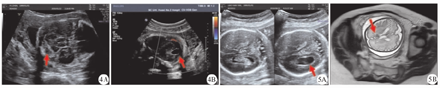

FICH胎儿超声对胎儿头颅进行初诊时,上述7例胎儿未被诊断为FICH,但是均提示颅脑结构异常,均表现为侧脑室增宽(轻、中度增宽各为5、2例);中、晚孕期复诊时,轻、中度增宽各为1、6例(图5)。

本组40例FICH胎儿的头颅MRI检查结果,15例可见脑室内出血,8例脑实质出血,16例生发层出血,1例硬膜下出血。中孕期胎儿超声MRI的FICH检出率分别为94.4%(17/18)与100.0%(18/18),晚孕期分别为72.7%(16/22)与100.0%(22/22)。中孕期胎儿超声与MRI的FICH诊断率比较,差异无统计学意义(P=0.500),晚孕期比较,差异有统计学意义(P=0.010)。

本研究结果显示,中孕期胎儿超声的FICH检出率为94.4%(17/18),晚孕期为72.7%(16/22)。本组40例FICH胎儿的超声检查结果显示,7例未提示FICH,究其漏诊原因如下。①中孕期被漏诊的1例FICH胎儿的超声检查结果与其MRI检查结果对比,可见其出血部位发生在少量出血的基底节区,出血范围小,而被漏诊。②晚孕期被漏诊的6例FICH的胎儿超声检查与MRI检查结果对比,可见2例出血量较少,2例发生在不易探查的超声颅骨近场区,2例出血吸收特征不典型,由于晚孕期胎儿颅骨钙化,超声声束近场区颅脑结构显示不清晰,也可能血块本身可动态发展,随胎龄增加被吸收而消失,或即使血块的范围保持不变,不同时期颅内回声发生变化,而被漏诊。

FICH的MRI具有较突出特征[17]。MRI对软组织分辨率高,可多切面及多序列成像,是诊断胎儿软组织异常的重要影像学手段[18]。MRI对FICH可精准定位,可判断脑实质损伤情况[5]。MRI虽然对FICH较为敏感,但是具有检查费用较高、易受胎动影响、不能实时动态成像、显示室管膜及脉络丛不及超声图像清晰等缺点[19],而且受试者合并幽闭恐惧症,体内含有金属等为MRI禁忌证[20],因此目前临床诊断FICH的首选检查手段仍是超声检查,对于超声检查切面显示困难者,再选择MRI作为补充检查。本研究结果显示,中孕期胎儿超声及MRI对FICH检出率比较,差异无统计学意义(P=0.500),这可能与中孕期超声对胎儿颅内结构显示清晰,颅脑扫查切面较多且标准有关;而晚孕期胎儿超声对FICH检出率低于MRI,并且差异有统计学意义(P<0.05),这可能为胎头位置低或已入盆、颅骨钙化等有关。